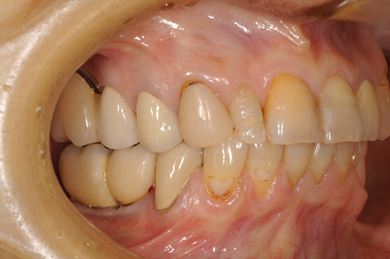

インプラントの症例写真 IMPLANT

骨再生インプラント治療+セラミック治療

| 治療内容 | インプラント6本(ソケットリフト)、ハイブリッドセラミック14本(ハイブリッドセラミック用土台5本、遊離歯肉移植術 | ||||||||||||||||||||||||||||||||

| 総治療費 | 2,751,445円 | ||||||||||||||||||||||||||||||||

| 治療期間 | 2年3ヶ月 |